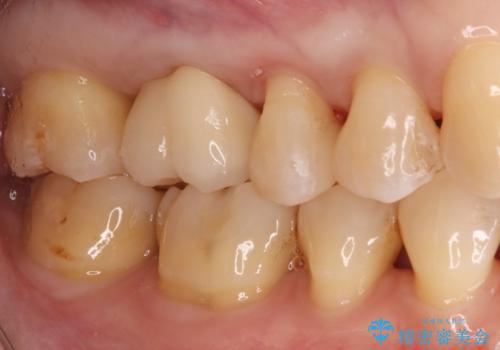

- 左上奥歯に入っている金属の詰め物(メタルインレー)の見た目を改善したいという主訴でご来院されました。お口の中の金属をなくしたいという患者様のご希望を踏まえ、天然歯に近い色と質感を持つセラミックインレーに交換する治療計画を立案。これにより、見た目の改善だけでなく、金属アレルギーのリスクを排除したメタルフリーの環境を実現することを目指しました。

治療では、まず古い金属のインレーを慎重に取り外しました。金属の下に隠れていた虫歯の再発がないかを確認し、歯を丁寧に形成。その後、精密な型取りから患者様の歯の色に合わせたオーダーメイドのセラミックインレーを作製しました。セラミックは、自然な光の透過性を持つため、周囲の歯と区別がつかないほどの美しい仕上がりとなります。適合性の高いセラミックインレーを装着することで、再発のリスクを抑えつつ、長年のコンプレックスだった銀歯がなくなり、笑顔でも気にならない自然な奥歯を取り戻していただけました。